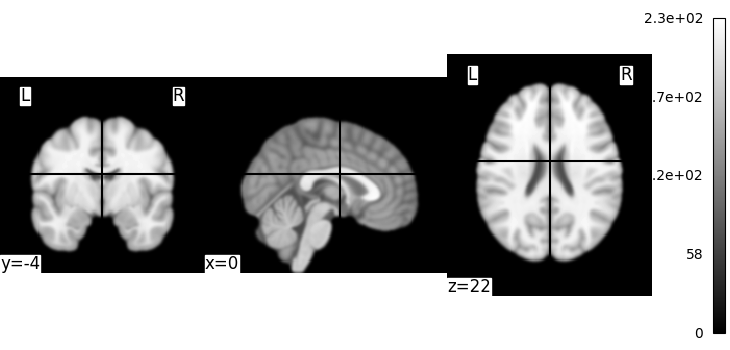

Simple image manipulation: smoothing¶

Let’s use an image-smoothing function from nilearn:

smooth_img

Functions containing ‘img’ can take either a filename or an image as input.

Here we give as inputs the image filename and the smoothing value in mm

from nilearn import image

smooth_anat_img = image.smooth_img(MNI152_FILE_PATH, fwhm=3)

# While we are giving a file name as input, the function returns

# an in-memory object:

smooth_anat_img

<nibabel.nifti1.Nifti1Image object at 0x7f36fa868eb0>

This is an in-memory object. We can pass it to nilearn function, for instance to look at it

<nilearn.plotting.displays._slicers.OrthoSlicer object at 0x7f36fa90c220>